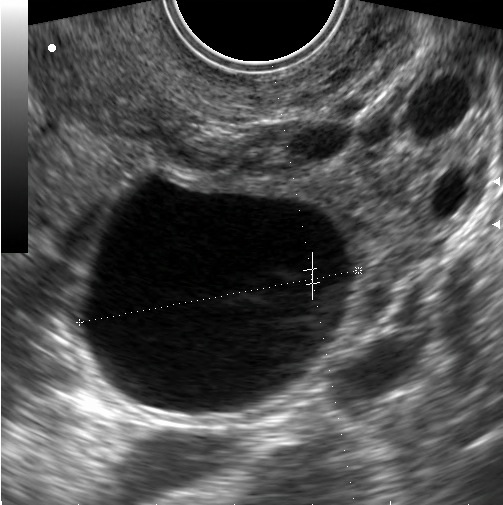

На этом узи снимке вы видете доминирующий фолликул преовуляторного диаметра, а именно от 19мм. Тесты на овуляцию показывают 2 полоски. Вторая полоска классически ярчает и пациентка уверена, что овуляция есть. Если мы посмотрим эту пациентку через 7-10 дней, скажем в промежуток от 21 до 25 дня, мы увидим такую картину:

Теперь как все было в реальности: Через день от узи 1, по факту мы видим все такой же фолликул. И на следующий день. И через день.

А вот к 5-6 дню от предполагаемой овуляции картинка начинает меняться, фолликул изменяет контур и приобретает гиперэхогенные перемычки, характерные для желтого тела.

Диагноз - лютеинизация неовулирующего фолликула